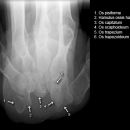

Handgelenk a.p.

Beurteilungskriterien

• Neigung der distalen Radiusgelenkfläche in der Frontalebene: 15 – 35°

• Längenverhältnis Radius – Ulna: Proc.styloideus radii überragt Gelenkfläche der Ulna um 9 –12mm (<9mm Ulna-Plusvariante, >12mm Ulnaminusvariante)

• Kontinuität der drei Karpalbögen:

Proximaler Bogen: proximale Gelenkflächenkonturen von Scaphoid, Lunatum und Triquetum

Mittlerer Bogen: distale Gelenkflächenkonturen von Sacphoid, Lunatum und Triquetum

Distaler Bogen: proximale Gelenkflächenkonturen von Capitatum und Hamatum

Fehlende Abgrenzbarkeit, Versatz oder Unterbrechung sind als pathologisch zu bewerten und deuten auf eine Luxation hin.

Trapezförmige Darstellung des Lunatum in Neutralstellung? Augenzeichen des Hamulus? Superposition von Pisiforme und Triquetum? Metacarpale III in Projektion innerhalb der Radiusgelenkfläche? Lunatum zu >50% über Radiusgelenkfläche? Cave: bei Radial- oder Ulnarduktion wandert das Lunatum in umgekehrter Richtung.

• M-förmiger Verlauf der Gelenkspalten der Carpometacarpalgelenke? Luxationsstellung in den Carpometacarpalgelenken (meist dorsale Luxation)?

• Gelenkspaltweiten des Radiocarpalgelenk 2 – 2,5mm, der Carpometacarpalgelenke 1 –2mm, distales Radioulnargelenk 2mm, Gelenksspaltweiten der Intercarpalgelenke 1,5 – 2mm

Cave: SL-Dissoziation (Ruptur des SL- Bandes, häufigste Gefügestörung): Terry-Thomas-Sign = SL-Spalt > 3mm, Siegelringzeichen = Ringförmige Transparenzminderung im mittleren Scaphoiddrittel durch orthograde Projektion der Taille infolge Rotation.

• Obliteration des Scaphoidfettstreifens?

• Täuschungsmöglichkeiten durch Vielzahl akzessorischer Ossikel (abgerundete, zirkulkär-geschlossene Kortikalis), geteilte Handwurzelknochen (Scaphoid, Lunatum, Pisiforme) und Gefäßkanälchen

• Target areas leicht zu übersehender Frakturen: distales Radioulnargelenk, Processus styloideus radii et ulnae, Basen der Metacarpalia (v.a. MCP I), Hamulus.

• Grundsätzlich gilt: unklare Verhältnisse ->CT-Indikation